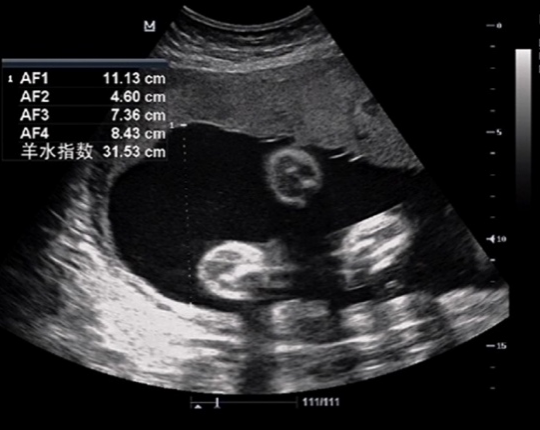

南方医院胎儿医学门诊接诊了一位34岁的孕妇,已妊娠31周余,产检做三级产科超声发现羊水过多、胎儿心包积液。在医生的建议下进行产前诊断,并进行了染色体核型和基因芯片检测,结果提示为: